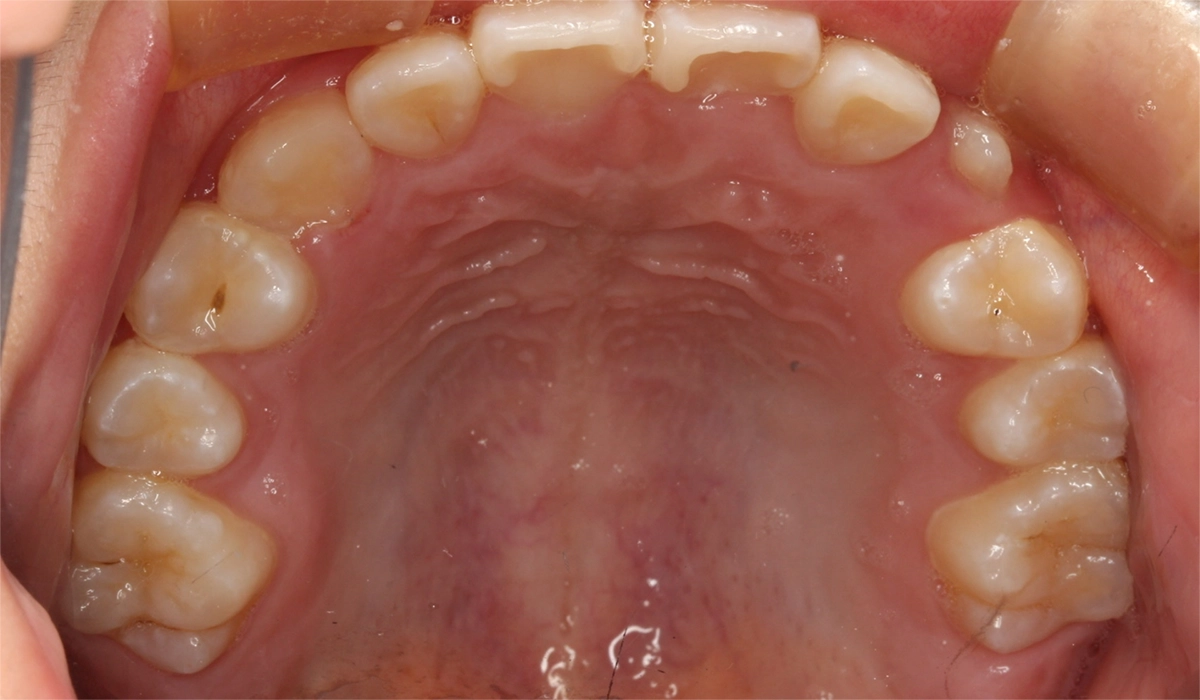

術前:上顎